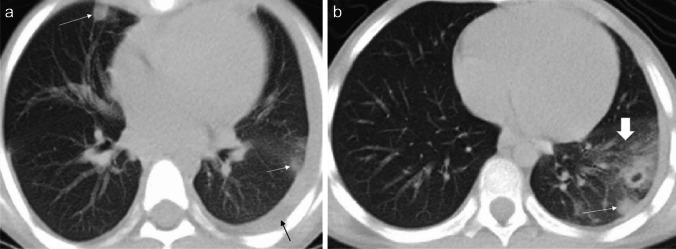

Fig. 7.

Axial non-contrast-enhanced lung window computed tomography images in a 7-year-old girl with paragonimiasis who presented to hospital with abdominal pain and subcutaneous nodules. a Image at the level of the mid lung zone shows ill-defined lung nodules (white arrows) and a left-sided pleural effusion (black arrow). b Image at the level of the lower lung zone shows ill-defined lung nodules (thin arrow) and alveolar opacification (thick arrow) (figure from “A retrospective clinical analysis of pediatric paragonimiasis in a Chinese children’s hospital from 2011 to 2019” by Qian et al.; licensed under CC BY 4.0; original cropped and annotated)